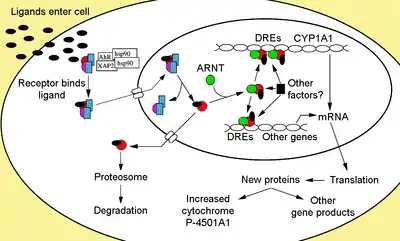

The aryl hydrocarbon receptor is a member of the family of basic helix-loop-helix transcription factors. AhR binds several exogenous ligands such as natural plant flavonoids, polyphenols and indoles, as well as synthetic polycyclic aromatic hydrocarbons and dioxin-like compounds. AhR is a cytosolic transcription factor that is normally inactive, bound to several co-chaperones. Upon ligand binding to chemicals such as 2,3,7,8-tetrachlorodibenzo-p-dioxin (TCDD), the chaperones dissociate resulting in AhR translocating into the nucleus and dimerizing with ARNT (AhR nuclear translocator), leading to changes in gene transcription.

Cytosolic complex

Non-ligand bound AhR is retained in the cytoplasm as an inactive protein complex consisting of a dimer of Hsp90,[28][29] prostaglandin E synthase 3 (PTGES3, p23)[30][31][32][33] and a single molecule of the immunophilin-like AH receptor-interacting protein, also known as hepatitis B virus X-associated protein 2 (XAP2),[34] AhR interacting protein (AIP),[35][36] and AhR-activated 9 (ARA9).[37] The dimer of Hsp90, along with PTGES3 (p23), has a multifunctional role in the protection of the receptor from proteolysis, constraining the receptor in a conformation receptive to ligand binding and preventing the premature binding of ARNT.[12][31][33][38][39][40] AIP interacts with carboxyl-terminal of Hsp90 and binds to the AhR nuclear localization sequence (NLS) preventing the inappropriate trafficking of the receptor into the nucleus.[41][42][43]

Receptor activation

Upon ligand binding to AhR, AIP is released resulting in exposure of the NLS, which is located in the bHLH region,[47] leading to import into the nucleus.[48] It is presumed that once in the nucleus, Hsp90 dissociates exposing the two PAS domains allowing the binding of ARNT.[40][49][50][51] The activated AhR/ARNT heterodimer complex is then capable of either directly or indirectly interacting with DNA by binding to recognition sequences located in the 5’- regulatory region of dioxin-responsive genes.[40][50][52]

Adaptive and innate response

The adaptive response is manifested as the induction of xenobiotic metabolizing enzymes. Evidence of this response was first observed from the induction of cytochrome P450, family 1, subfamily A, polypeptide 1 (Cyp1a1) resultant from TCDD exposure, which was determined to be directly related to activation of the AhR signaling pathway.[74][75][76] The search for other metabolizing genes induced by AhR ligands, due to the presence of DREs, has led to the identification of an "AhR gene battery" of Phase I and Phase II metabolizing enzymes consisting of CYP1A1, CYP1A2, CYP1B1, NQO1, ALDH3A1, UGT1A2 and GSTA1.[77] Presumably, vertebrates have this function to be able to detect a wide range of chemicals, indicated by the wide range of substrates AhR is able to bind and facilitate their biotransformation and elimination. The AhR may also signal the presence of toxic chemicals in food and cause aversion of such foods.[78]